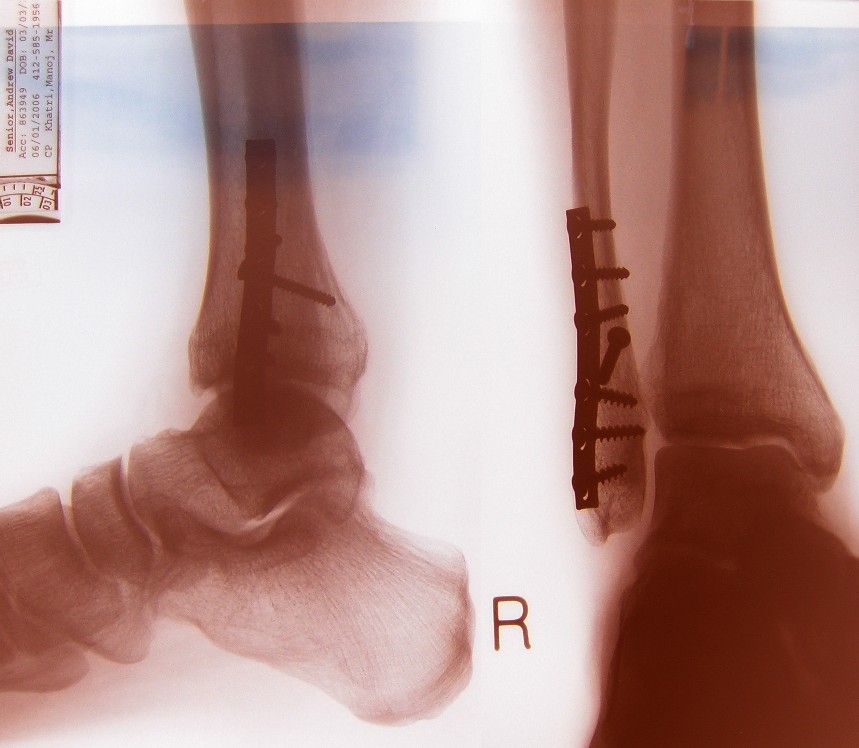

My Smashed-up Ankle

The amulance blokes were great. I had "gas-and-air" (air is a gas ?), which did make me laugh, but also made me vom next day. Preston Royal did a fine job or re-jigging it as soon as we arrived. At 1am Sunday morning there was a suprising lack of drunken (except me) fighting chavs there. Dislocated tibia, spriral fracture of tibia, "Weber B" fracture of fibula. You can see the fibula broken cleanly twice. Strangely, it never really hurt, although I'd had a good dose of beer-anaesthetic at the time.

The fibula cracks weren't calcifying, so they surgically put in a stainless steel plate to bring the bits together whilst they heal. This also didn't really hurt after the op, though I was warned it would a lot. I think the surgical team also accidentally replaced my calf muscle with a small floppy bag of liquid. After 24 hrs to let the big nasty scar heal a bit, put on pot #3. Colour choice by neice Hannah.